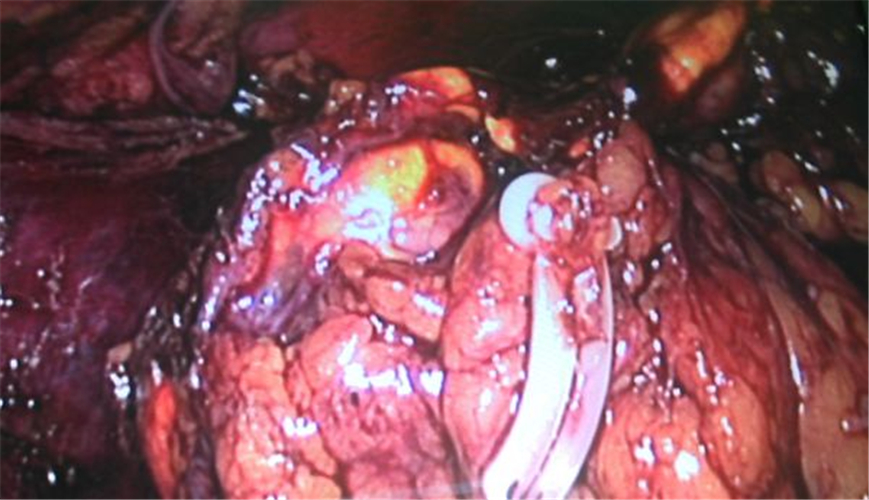

左側腎上腺腫瘤手術